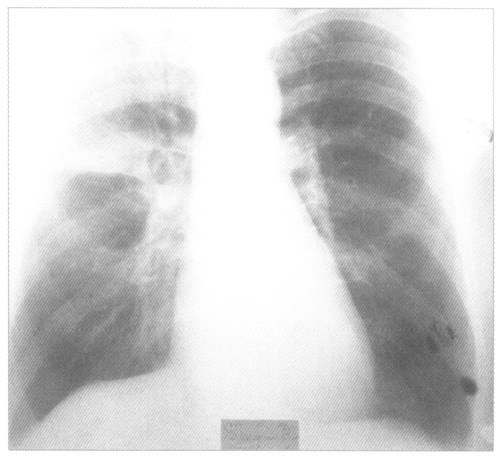

Крупозная пневмония на рентгенснимке